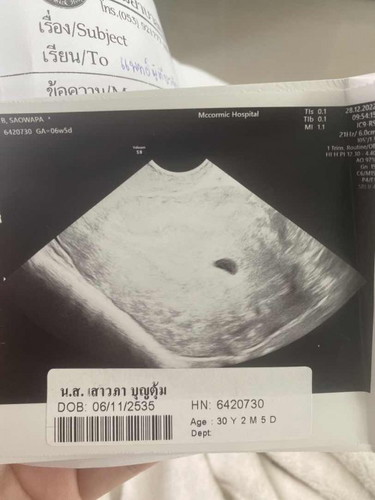

ใครมีประสบการณ์แบบบ้านนี้ไหมคะ ท้องแรกน้องโครโมโซมคู่ 21 เกิน ยุติการตั้งครรภ์ไปตอน เดือนมีนาคม 2565 ท้องสองไข่ตกตอนต้นเดือนธันวาคมไปซาวด์สองครั้ง สรุปน้องเป็นท้องลม รู้สึกหดหู่ เสียใจมากค่ะ หมอให้รอ 2 อาทิตย์ให้น้องหลุดเอง แต่ถ้าไม่หลุดให้ไปโรงบาลเพื่อทำการเหน็บยาค่ะ

บ้านนี้ก็เป็นค่ะ 11วีคเจอแต่ถุงตั้งครรภ์ แล้วมีเลือดออกด้วย คุณหมอบอกว่าน่าจะเป้นท้องลม

ซาวด์ตอนเช้าทั้งสองทางเลยค่ะ ไม่เจอน้องเลยค่ะ ก่อนหน้านี้ 2 อาทิตย์ก็ไม่เจอค่ะ